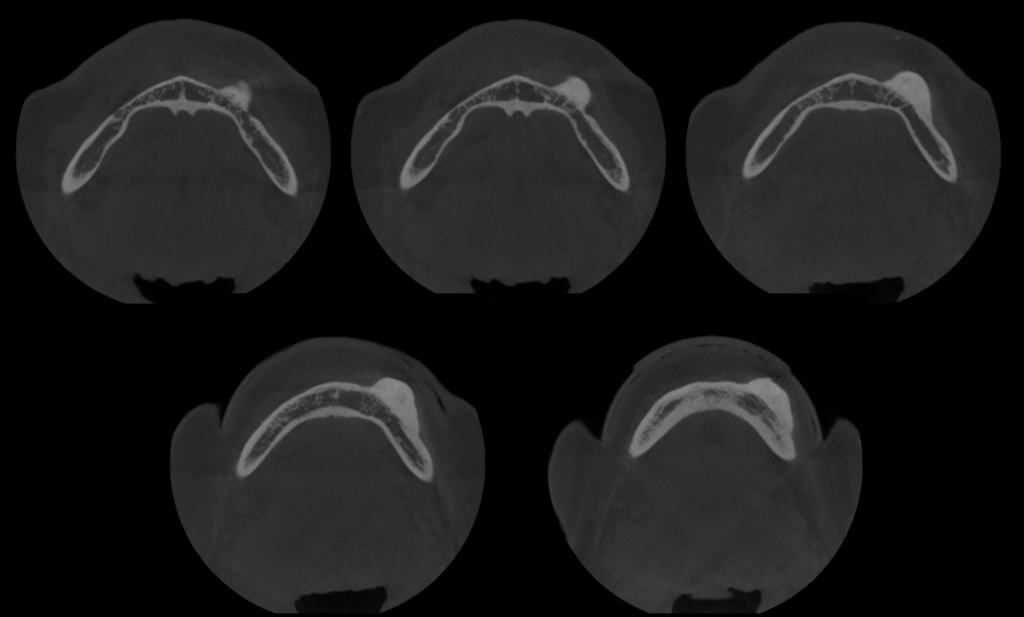

A la evaluación de la tomografía volumétrica de campo 10 x 10 se observa la presencia de la misma imagen hiperdensa a nivel mandibular del lado izquierdo y por vestibular de limites definidos y base pediculada a la altura de las piezas 33 y 34 y muy cerca al conducto dentario inferior compatible con osteoma mandibular.

CORTES AXIALES